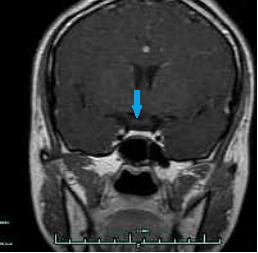

CASE3 病人***男性,30岁,因“性功能下降、不育5年”入院,入院诊断垂体泌乳素微腺瘤。

在全麻下行经鼻蝶内镜下垂体微腺瘤切除术,术后病人泌乳素指标恢复正常,性功能有一定改善。(红色箭头示黑色圆点为垂体微腺瘤;蓝色箭头示术后3个月复查未见肿瘤显示)